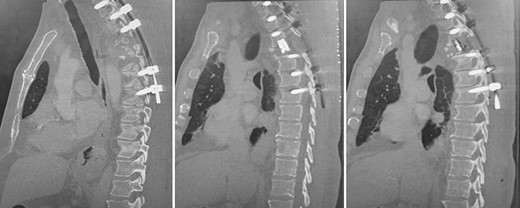

Spinal images are presented in Figs 1–6. Cross-sectional imaging revealed no other neoplastic lesion. He received dexamethasone 10 mg bolus then 4mg four times daily with appropriate proton pump inhibitor coverage. Due to no distinguishable major arterial feeder upon review of the imaging jointly with the neuroradiologist, pre-operative embolization was not attempted. The following morning, he underwent posterolateral right costotransversectomy, ligation of the ipsilateral T4 nerve root, T4 vertebrectomy and insertion of an expandable titanium cage with T1–T7 pedicle screw fixation (Figs 7 and 8). Post-operatively his pain improved to VAS 2/10 and motor power in his left lower limb improved to MRC grade 4/5. The patient was discharged home Day 10 post-admission with physiotherapy.

Post-operative, sagittal CT images of the T1–T7 pedicle screw fixation and expandable titanium cage in situ.